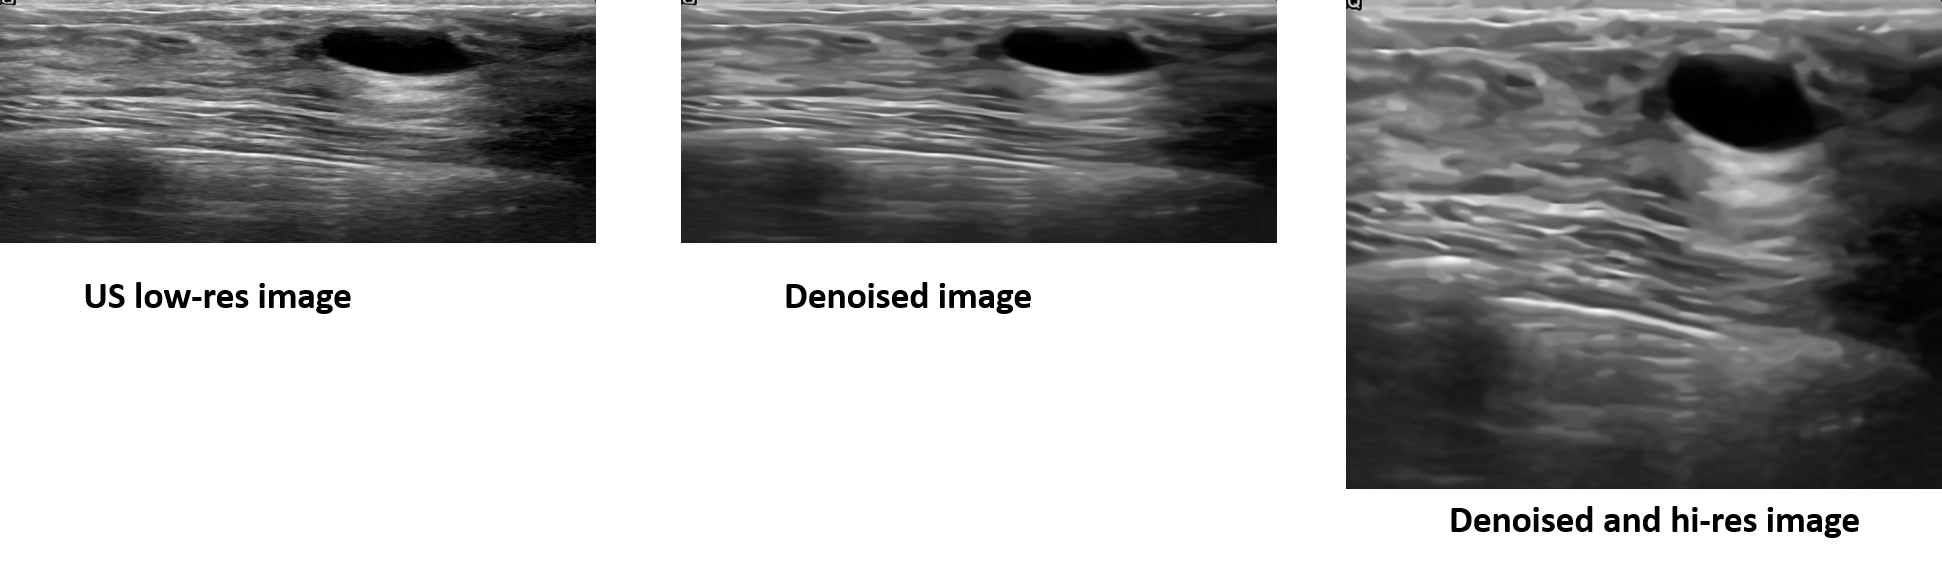

Transversal to all the imaging modalities integrated within the MS-DT framework, such as ultrasound, MRI, CT, we incorporate real-time denoising and super-resolution techniques to enhance image quality and diagnostic value. These processes are implemented using deep learning models that are adaptable to different data types and anatomical regions. Real-time denoising reduces acquisition noise while preserving fine anatomical details, facilitating clearer interpretation and more reliable feature extraction across imaging sources [18]. Similarly, real-time super-resolution enhances both spatial and temporal resolution, allowing for the extraction of detailed structural and functional information in an interactive and clinically usable form [19]. By applying these enhancement methods consistently across modalities, we ensure high-quality data integration and improved performance of subsequent processing steps such as segmentation, registration, and feature analysis.

- [18] Simone Cammarasana, Paolo Nicolardi, and Giuseppe Patanè. Real-time denoising of ultrasound images based on deep learning. Medical & Biological Engineering & Computing, 60(8):2229–2244, 2022.

- [19] Simone Cammarasana, Paolo Nicolardi, and Giuseppe Patanè. Super-resolution of 2d ultrasound images and videos. Medical & Biological Engineering & Computing, 61(10):2511–2526, 2023.